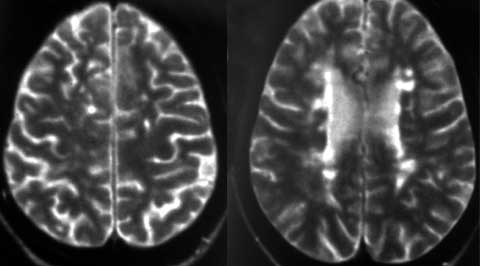

Оценка динамики активности ремиттирующего и прогрессирующего рассеянного склероза.

Рис. 2. Обширный атрофический процесс с расширением желудочковой системы, субарахноидальных пространств с очагами демиелинизации при вторично-прогрессирующем РС. (Слева) - полушария, (Справа) - ствол головного мозга.